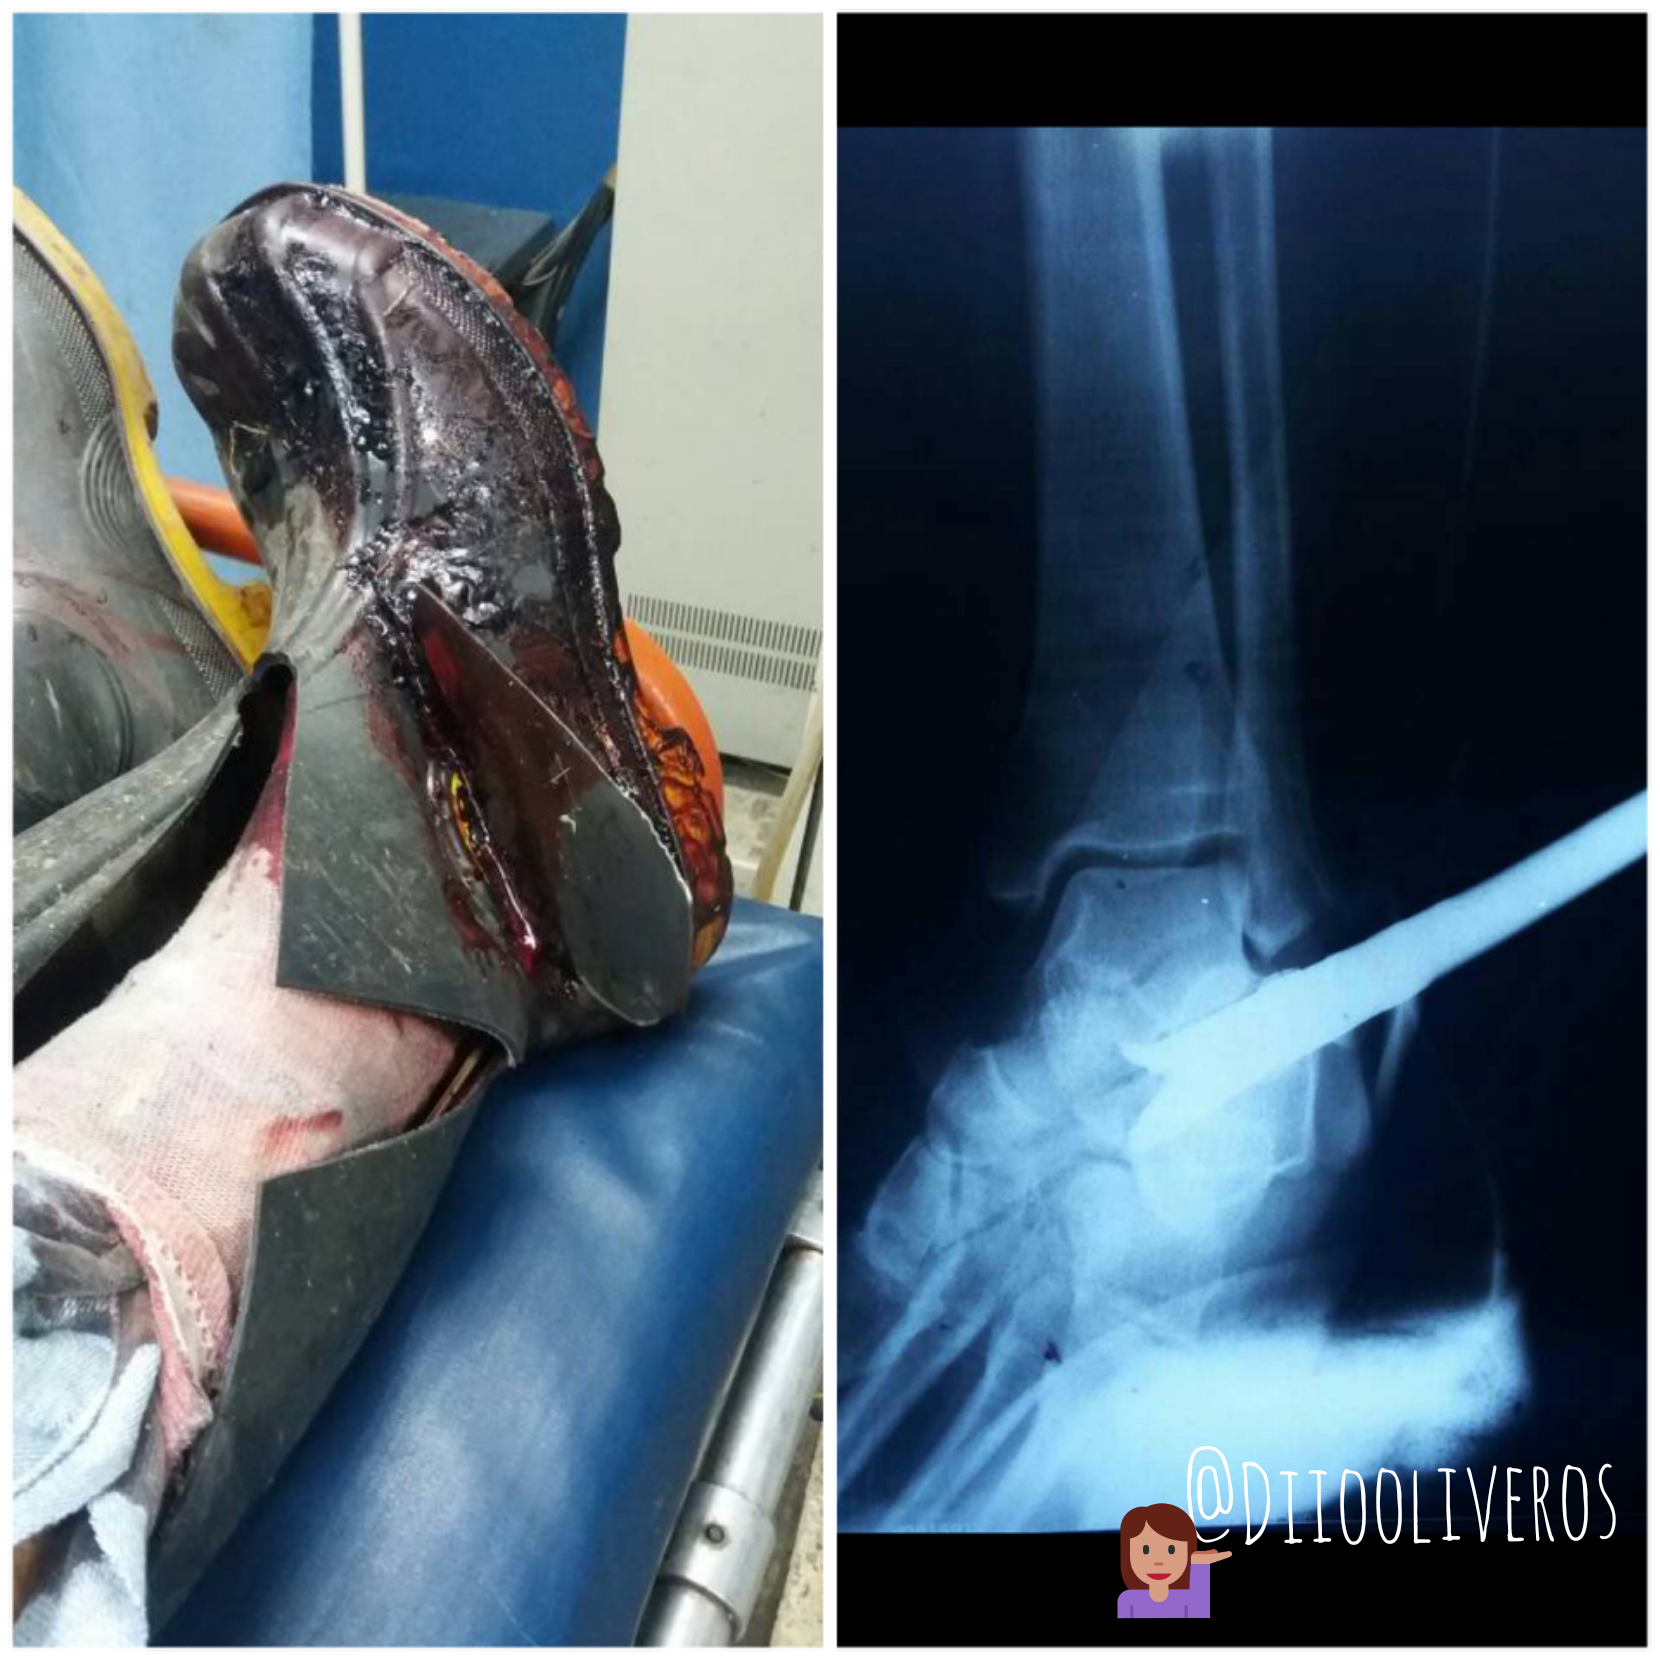

Auch! cuchilla de cortagrama en pie. Accidente visto desde un RX

Como estan mis queridos amigos de la comunidad steemit. Aca les traigo 2 fotografias de un paciente que ingresó a nuestra sala de emergencia de RX , en Valencia-Venezuela. El…

Accidente por Cuerpo Extraño en miembro inferior (pie)

Saludos mis queridos Steemianos y Steemianas ! En esta oportunidad les quiero mostrar estas imagenes que logre captar en el servicio de radiologia donde trabajo. Quise…